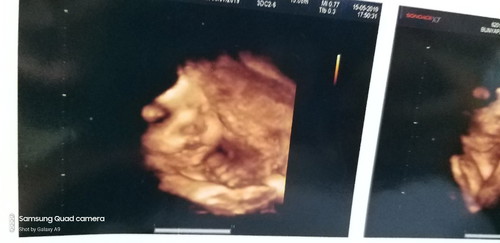

กำหนดคลอด 9 ก.ค. 62

วันนี้ 39 week +3 ไม่มีวี่แวว การปวดท้องใดๆ เลย มีความอยากเห็นหน้าลูกสาวแล้ว คะ